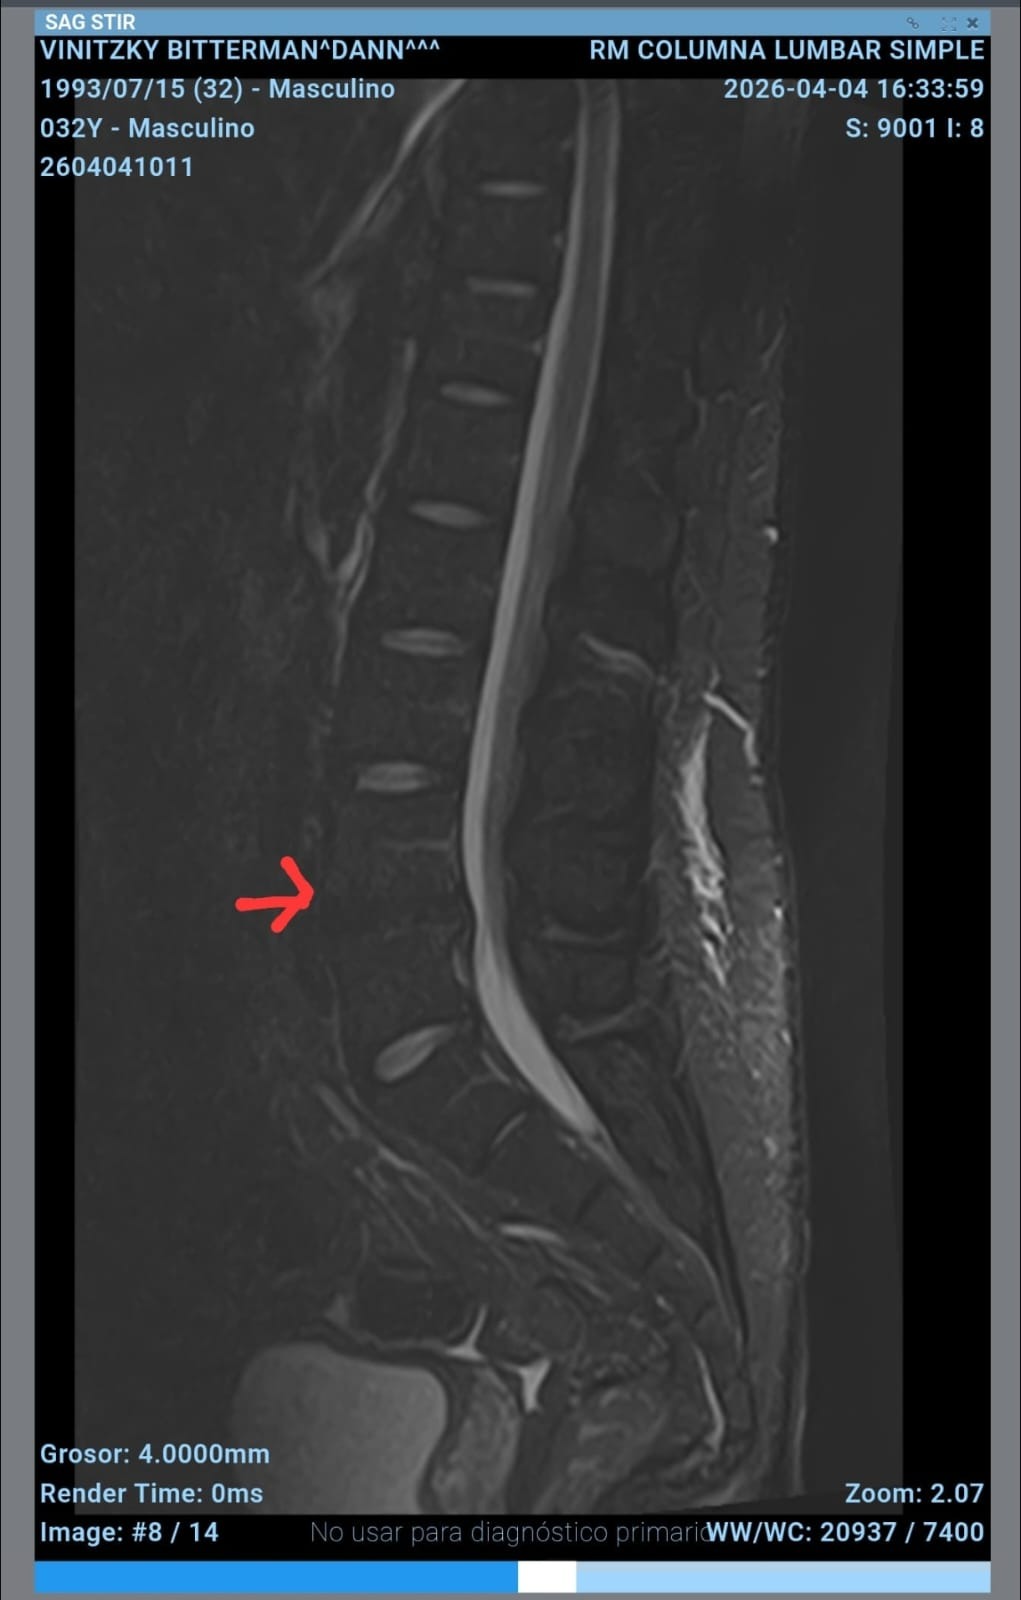

A mis 32 años estoy enfrentando la prueba más dura de mi vida. Tengo un problema severo en los discos L4 y L5 que está afectando a mis nervios y mi movilidad. El dolor es constante, y hoy me impide seguir adelante.

Necesito una cirugía urgente para no perder la posibilidad de caminar y recuperar mi vida. Mis ganas de salir adelante siguen intactas, pero los costos están fuera de mi alcance.